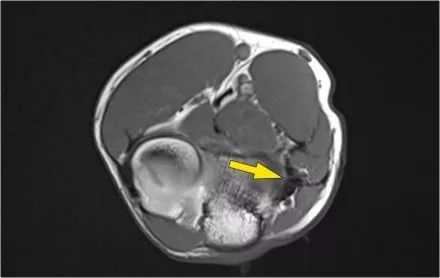

MR-关节造影证实了骨软骨病变。在肱骨和骨软骨病变之间存在钆造影剂,这表明它是不稳定的。注意轴向图像上看到的碎片。